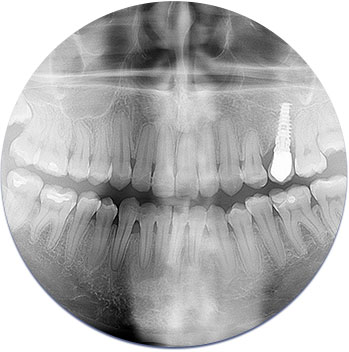

Digital X-Rays

Lower radiation and more detailed images are the two primary benefits of digital (vs. traditional) x-rays. In addition, these systems allow us to use smaller sensors which make things more comfortable for you. Finally, they enable us to study the images as soon as they are taken, and we can develop next steps in our treatment plans almost instantly.